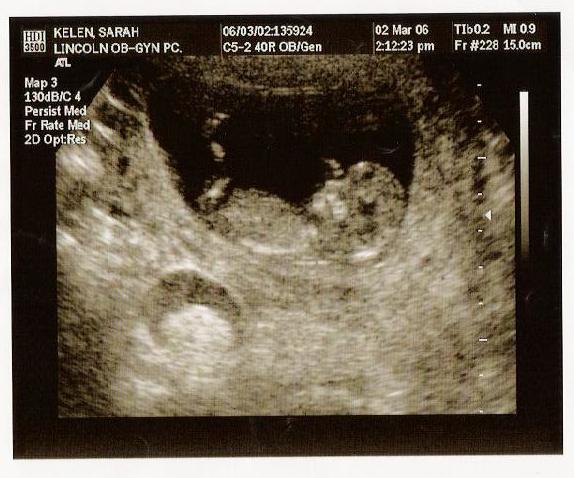

Sarah and Ken will also be having a baby in September. So far it's hard to tell which one of them the baby looks like, but it sure looks cute to them. (Can't tell what you're looking at? The head is on the right; it's waving and kicking a leg.)